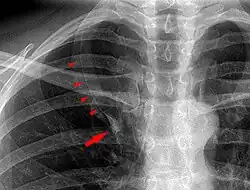

In human anatomy, an azygos lobe is a normal anatomical variation of the upper lobe of the right lung.[1] It is seen in 0.3% of the population.[2] Embryologically, it arises from an anomalous lateral course of the azygos vein,[3] in a pleural septum within the apical segment of the right upper lobe or in other words an azygos lobe is formed when the right posterior cardinal vein, one of the precursors of the azygos vein, fails to migrate over the apex of the lung and penetrates it instead, carrying along two pleural layers as the azygous fissure, that invaginates into the upper portion of the right upper lobe.[1]

An azygos lobe is usually an incidental finding on chest x-ray or CT scan. It is asymptomatic and not associated with any morbidity.[4][5] However, it can cause technical problems in thoracoscopic procedures.[6] The presence of the azygos lobe could alter the normal location of the superior vena cava or may be associated with other anomalies, including esophageal atresia or intrapulmonary right brachiocephalic veins.[7]